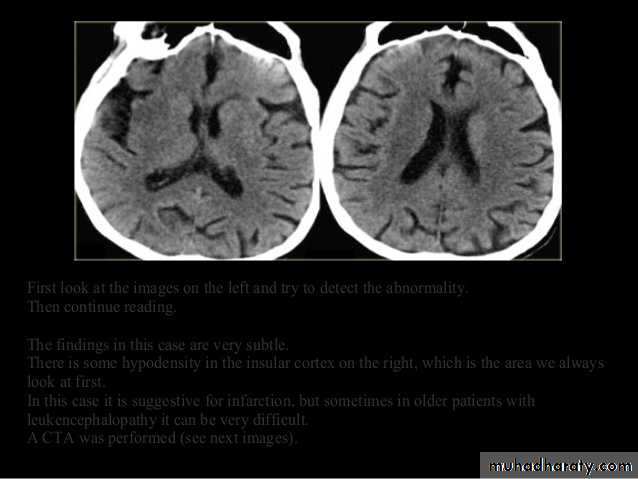

• Role of CT and MR in patients with stroke• Early CT and MR signs of infarction

• Exclude hemorrhage• Differentiate between irreversibly affected brain tissue and reversibly impaired tissue (dead tissue versus tissue at risk)